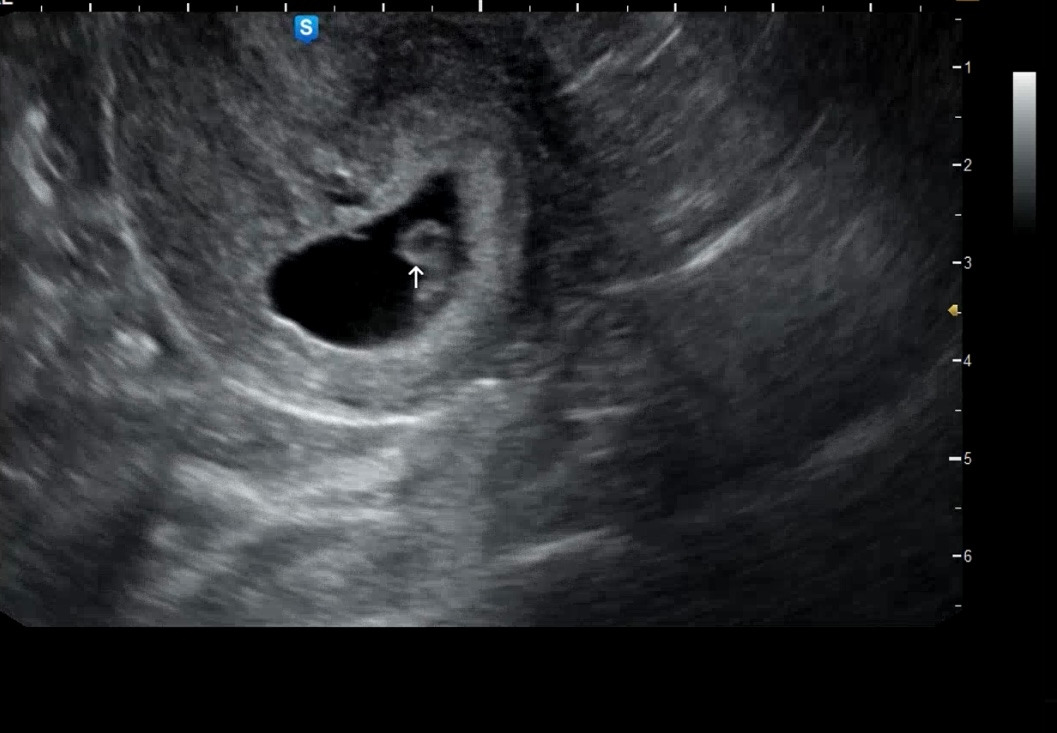

7주차: 아직 잘 안 보인다. 머리가 아니라 난황이라고 설명해 주셨지만 꼭 머리 같아...